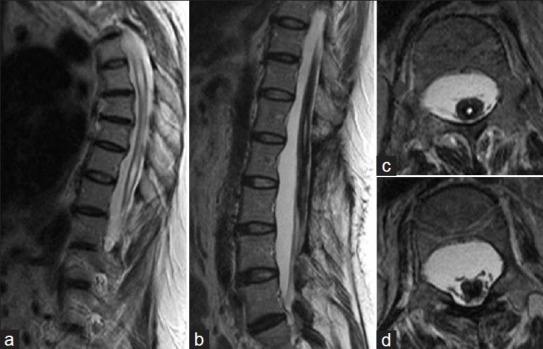

A 39-year-old female with Noonan syndrome underwent foramen magnum decompression and a cervical syrinx-subarachnoid shunt for Chiari type I malformation-associated syringomyelia 7 years ago. She presented progressive gait deterioration and acute urinary dysfunction, indicating conus medullaris syndrome. Initial magnetic resonance imaging revealed massive hemorrhage in the intrasyringeal cavity of the conus medullaris. The patient underwent surgical removal of the intrasyringeal hematoma and her neurological symptoms improved postoperatively.

一名39岁患有努南综合征的女性7年前因I型Chiari畸形相关的脊髓空洞症接受了枕骨大孔减压术和颈段脊髓空洞-蛛网膜下腔分流术。她出现进行性步态恶化和急性排尿功能障碍,提示圆锥马尾综合征。最初的磁共振成像显示圆锥马尾脊髓空洞腔内大量出血。患者接受了脊髓内血肿手术清除,术后神经症状改善。